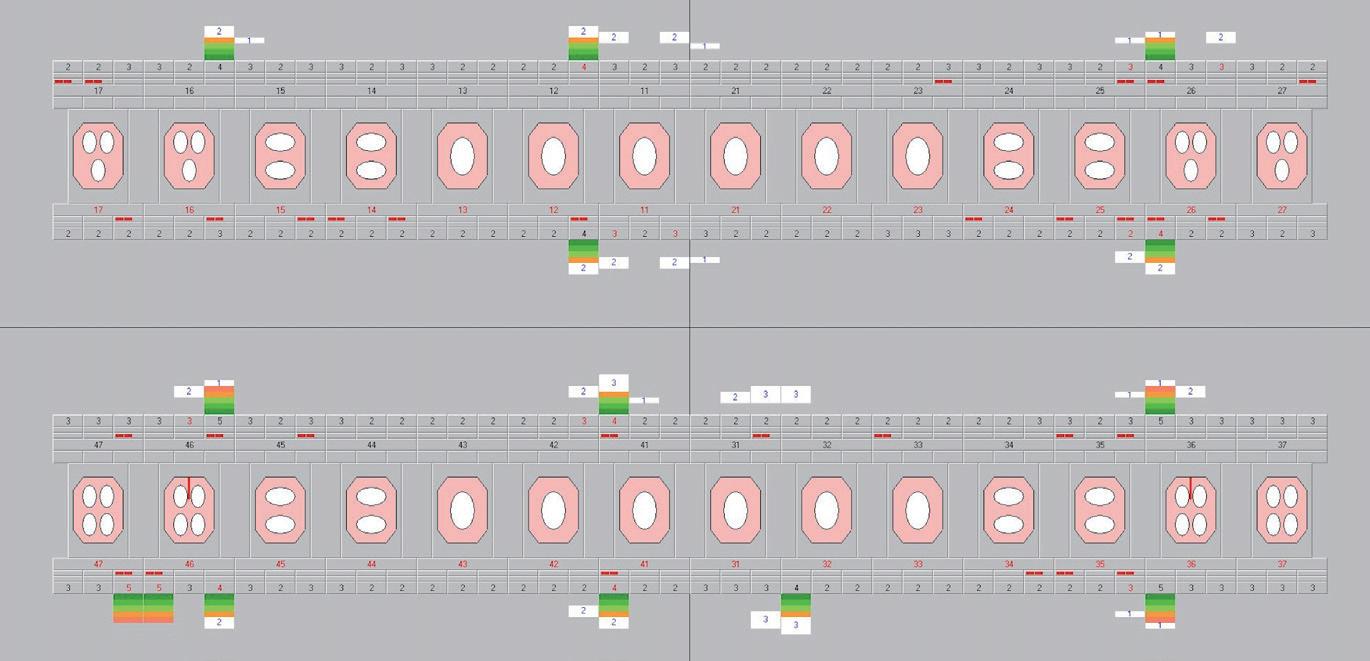

Regeneratie van het parodontium? Door de jaren heen zijn er regelmatig röntgenfoto’s gemaakt om te beoordelen hoe het bot zich heeft hersteld na het uitvoeren van de behandelingen. Opvallend is de vergelijking tussen de röntgenfoto’s d.d. 30-11-16 (intake) en 9-6-17 (evaluatie na initiële therapie), waar er duidelijk is te zien dat het komvormige verloop van de botdefecten afneemt en er ‘botingroei’ plaatsvindt. Ook zien we een corticalizering van de botrand ontstaan. Deze ontwikkeling is nog duidelijker zichtbaar na het uitvoeren van de regeneratieve chirurgie en op de röntgenfoto’s d.d. 14-2-20 (herbeoordeling na 3,5 jaar) is een verdere reductie van de angulaire botdefecten te zien (Afbeelding 13 en 14). Kunnen we nu spreken van regeneratie van het verloren parodontium? Dat is zonder histologisch onderzoek niet met zekerheid te stellen. Toch kunnen we op basis van de klinische metingen, de ondiepe pockets zonder bloeding en röntgenologisch herstel van het botdefect met vrij grote zekerheid aannemen dat er herstel is opgetreden.

Afbeelding 13. Röntgenologisch beeld Intake (30-11-16) Afbeelding 14. Röntgenologisch beeld herbeoordeling na 3,5 jaar (14-02-20)

Ruim één jaar later komt een stralende jonge vrouw, van inmiddels 19 jaar oud, de behandelkamer binnengelopen. We starten met het opnemen van de parodontiumsta tus en kunnen haar direct complimenteren met een zeer goede mondhygiëne. Ze heeft heel erg haar best gedaan en haar moeder bevestigt dat ze dit ook dagelijks zo volhoudt. De parodontiumstatus toont voornamelijk ondiepe pockets, slechts lo kaal nog licht verdiepte pockets en een bloedingsscore van 18% (Afbeelding 11 en 12). Voorheen als brenger van het slechte nieuws zijn we nu trots op haar. Eindelijk kunnen we haar na ruim drie jaar paro dontale zorg vertellen dat de verwijzing naar een orthodontist nu verantwoord is. Als beloning voor al haar moeite werd de verwijsbrief daarom ook direct geschreven.